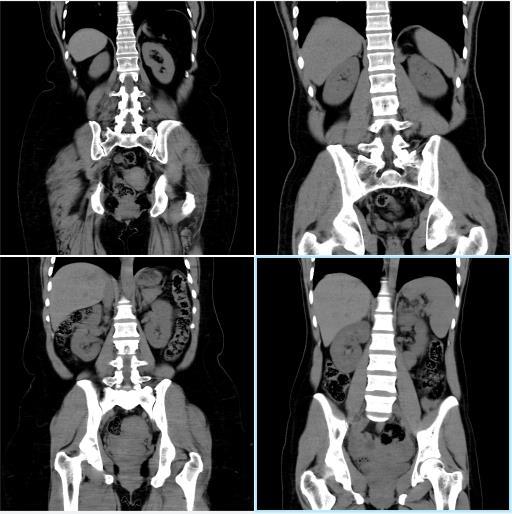

The dataset comprises CT scan images of kidneys, categorized based on the presence or absence of kidney stones. To ensure consistency in model training, preprocessing techniques such as image resizing, normalization,andaugmentationwereapplied.Theimages were resized to a standard dimension suitable for deep learningmodels,andnormalizationensuredthatpixelvalues remained within an optimal range. Data augmentation techniques were selectively used to enhance model generalizationandpreventoverfitting.

The dataset used for training contains CT scan images labeled according to the presence of kidney stones. These imageswerepreprocessedandaugmentedtoensurethatthe modelcouldgeneralizewellacrossvariousunseendata.The preprocessing steps involved resizing images to 224x224 pixels, which is the required input size for MobileNetV2. Normalizationwasappliedtoscalepixelvaluestoarange suitable for training deep learning models. Data augmentation techniques, such as random rotations, flips, and contrast adjustments, were used to increase the diversity of the dataset, which helps the model perform betterunderreal-worldconditionswhereimagesmayvary inorientation,brightness,andnoise.